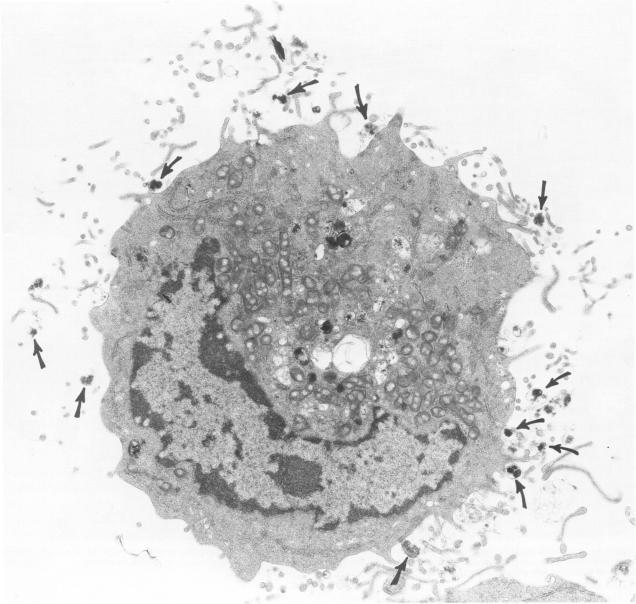

Antigen-induced, IgE-mediated degranulation of cloned immature mast cells derived from normal mice.

Cloned, immature mast cells derived from normal mice were passively sensitized with mouse monoclonal IgE antibodies with specificity for DNP, and then stimulated to degranulate with DNP35-HSA. Cells were fixed for transmission electron microscopy or recovered for quantitation of histamine release at various intervals up to 30 minutes after antigen challenge. The cloned mast cells rapidly extruded the contents of their immature granules (dense progranular material and membrane-bound vesicles) to the exterior via multiple openings in the plasma membrane. Degranulation was associated with striking activation of the cell surface, characterized initially by elongation of surface processes, as well as by close approximation of strands of rough endoplasmic reticulum to the cell surface and by the development of coated pits. At later times after stimulation, degranulated mast cells had released nearly all of their granules and exhibited angular surfaces lacking elongated processes. These findings demonstrate for the first time that cloned, immature mast cells, like their mature counterparts, can undergo classic morphologic release reactions involving exocytosis of granules.